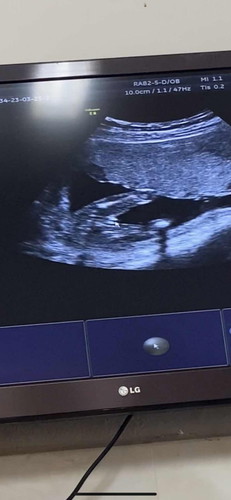

แม่ๆช่วยดูหน่อยคะ ซาวด์ดูเพศตอน16w3d หมอยืนยันว่าผู้หญิง แม่ๆว่า ผญ-ผช คะ👶🏻😂🥰

แม่ๆว่า ผู้หญิงหรือผู้ชายคะ ช่วยดูให้มั่นใจหน่อยคะ🥰😂

กลีบชัดอยู่นะ ตามหมอไปก่อนค่ะ